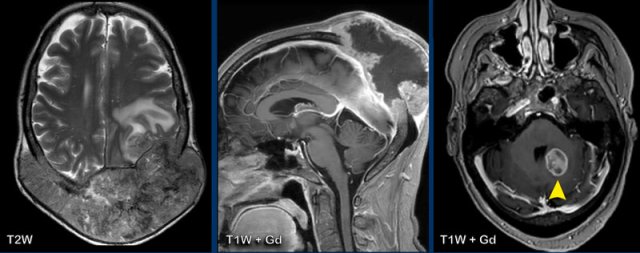

These images are of a 9-year old child who presented with headache.

Images

there is a large cystic posterior fossa mass with compression and

obstruction of the fourth ventricle and brainstem.

A solid contrast enhancing

nodule is present, as well as enhancement of the cyst wall.

Conclusion

Most likely diagnosis at this age is a pilocytic astrocytoma

These images are of a 3-year old child who also presented with headache.

There are two important findings.

Take a closer look at the images and then continue reading.

Large cyst with enhancing nodule in the posterior fossa..

Notice that the wall of the cyst enhances.

The nodule is not located on the pial side (inner part of the meninges) unlike in a hemangioblastoma.

Most likely diagnosis at this age is a pilocytic astrocytoma.

The enhancing wall is part of the tumor and needs to be resected.